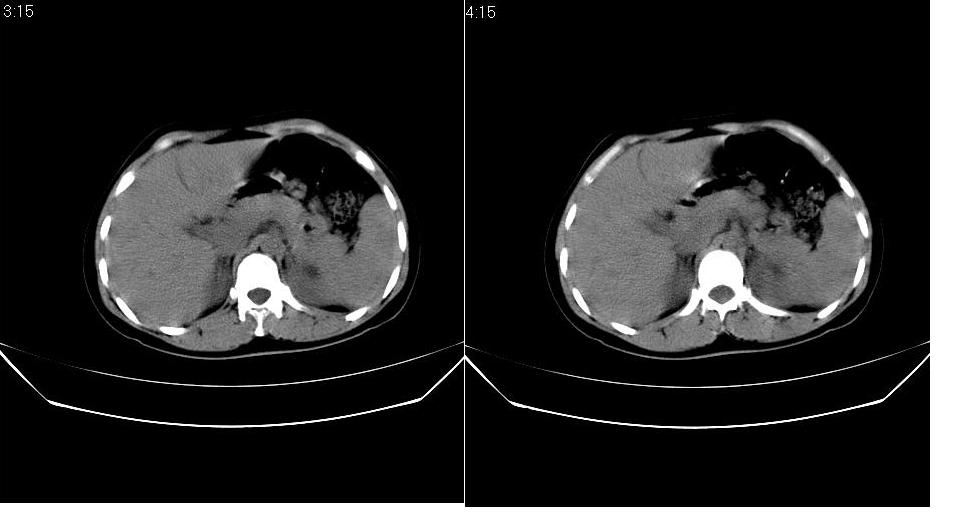

以下是引用求知若渴在2007-9-10 20:08:00的发言:[br]病变以脂肪成分为主,应该是错构瘤。另肝内胆管结石

以下是引用xulianj在2007-9-10 20:51:00的发言:[br]错构瘤,支持。含脂肪成分较多,证明较为成熟。

以下是引用齐原在2007-9-10 20:10:00的发言:[br]病变以脂肪成分为主,应该是错构瘤。另肝内胆管结石

以下是引用王仕学在2007-9-10 21:34:00的发言:[br]有脂肪密度,哪怕是一点点,首先考虑错构瘤。还是增强吧,好说些!